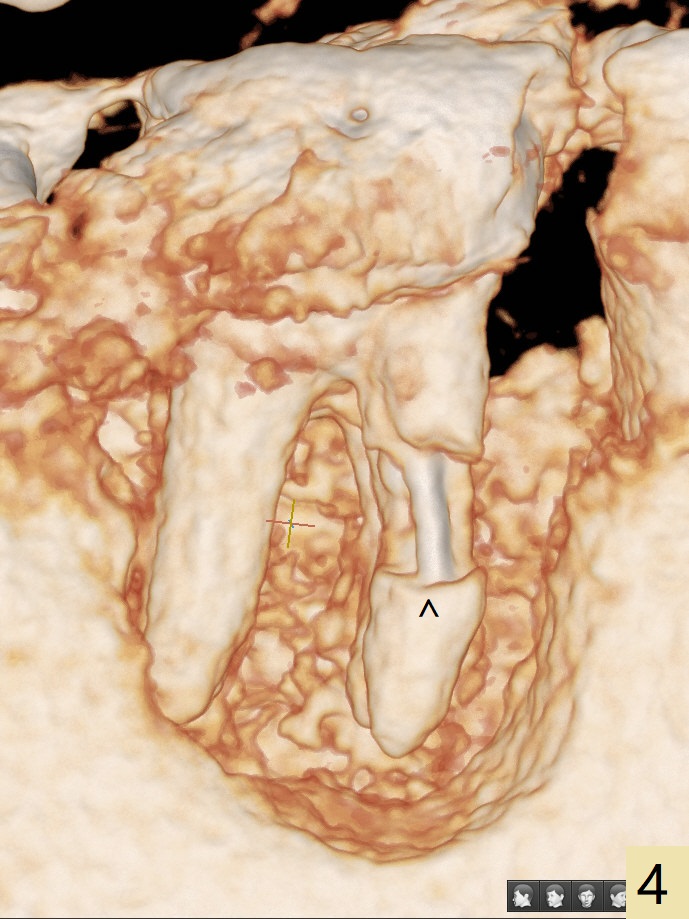

A 47-year-old man has poor dentition. The tooth #31 needs RCT, while #30 has severe PARL, especially mesial (Fig.1 M). The buccal roots are exposed (Fig.2). Between the exposed roots is the septal gingiva, which will be saved for buccal soft tissue repair (Fig.3 *). The septal gingiva will keep in place (not to be transferred) so that the recession will disappear by epithelial regrowth from the nearby gingiva (Fig.3' arrows) over the bone graft and PRF. The provisional should be fabricated to cover the soft tissue defect (Fig.3'' yellow area). In fact the mesial root fractures (Fig.4 ^), as related to the severe bony defect. There seems to be enough lingual bone to hold a 4x13 mm implant (Fig.5 green). Sticky bone (Fig.6 red circles) and PRF (blue) are to be used to repair the hard and soft tissue defects following an immediate provisional (Fig.5,6 yellow outline). Extra layer of acrylic (Fig.6 orange) will be used to cover the PRF buccally. The base of the buccal plate is thick (Fig.6 *); mesial portion appears to be denser (Fig.7 black *) than the distal one (white *). Decortication will be done if hemorrhage is insufficient. Fig.8 is a coronal section of the socket (B: buccal). Extraction (Fig.9 black area) will most likely result in a knife edge ridge. Extraction with bone graft may not fare better, as it is easy to lose the graft considering missing buccal hard and soft tissues.